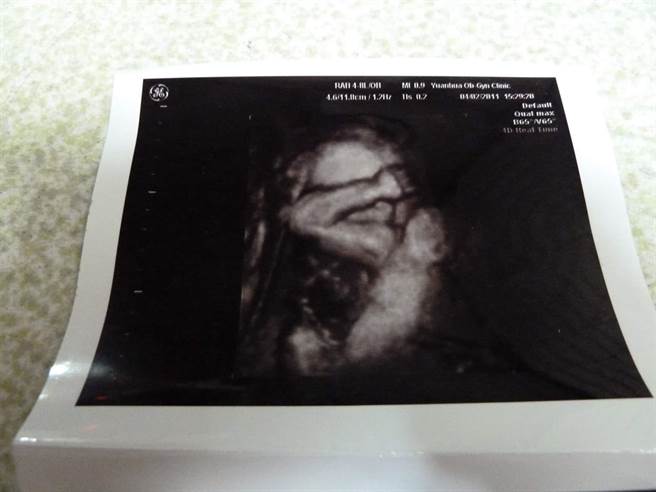

这位爸爸9日在脸书「爆废1公社」上表示,当年和跟老婆都在军职服务,在老婆怀孕时,意外在超音波照中惊见还在胎内的儿子做起「仰卧起坐」。从该超音波照还能看到,胎儿用双手托着后脑勺,做着相当标准的仰卧起坐姿势,还顺便秀一波粗壮厚实的肌肉。

照片曝光后,网友惊呼表示,「天生麒麟臂」、「居然还有肌肉!」、「这么小就秀肌肉」、「这个手是不是有点强壮?」还有人开玩笑说,「胎教就看莒光园地吧」、「胎教做的好」、「在肚子里就开始训练」、「还没出生就在为军旅生活做准备了,有那么急吗?」